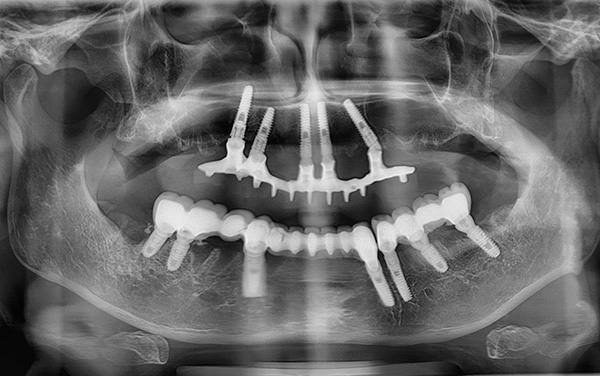

A foto abaixo mostra os implantes removidos da mandíbula:

Nas pequenas situações em que, por alguns motivos, dependendo ou não do médico, os implantes instalados na mandíbula são rejeitados, ocorre uma diminuição banal no tecido ósseo. Essa diminuição óssea no futuro pode ser facilmente compensada por sua restauração artificial usando um enxerto ósseo.